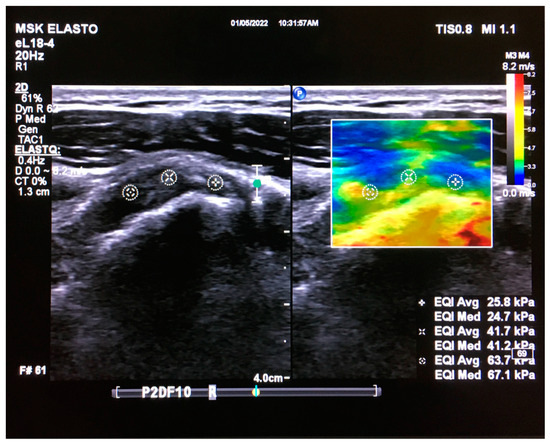

The conventional B-mode ultrasound image was displayed on the left side of the screen adjacent to the color-coded real-time elastogram on the right side of the screen. The transparency of the color was optimally adjusted to allow the underlying grayscale image to be visible through the superimposed color map. The color code displayed the relative stiffness of the tissues within the ROI, which ranged from blue (soft) to red (stiff). Green and yellow indicated medium elasticity (Figure 1).

Figure 1. Coronal real-time ultrasound elastography image of the supraspinatus tendon in a healthy young adult. B-mode ultrasound image (left) and ultrasound elastogram (right). The elasticity was measured at the proximal (+), middle (×), and myotendinous (*) parts of the tendon. A circular ROI with a diameter of 5 mm was manually applied to measure the tendon’s elasticity. Each measurement included the average and median of the elasticity of this circular ROI of the tendon in the rectangular ROI (which varied in size), focusing on the central part of the tendon. The image was obtained from the University of Washington Medical Imaging database with the required permissions.